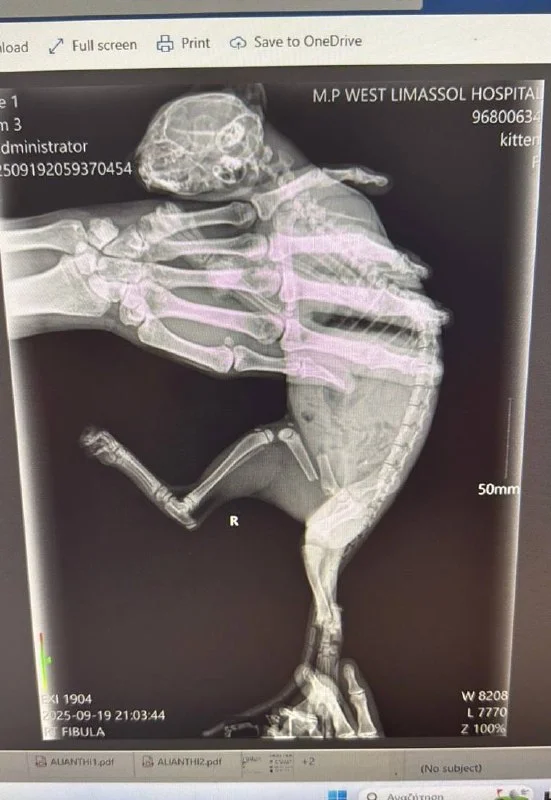

В клинике сделали повторные рентгены в доп проекциях , картина была лучше.🙏

Посмотрели сердечко - слава Богу, сердечной недостаточности нет 🥹

Доктор Наталья нас очень пожалела, взяла за всё - 50 евро 🥹💔 спасибо, добрый доктор!!!!♥️♥️♥️

Пришли к выводу, что случился астматический криз 💔😭